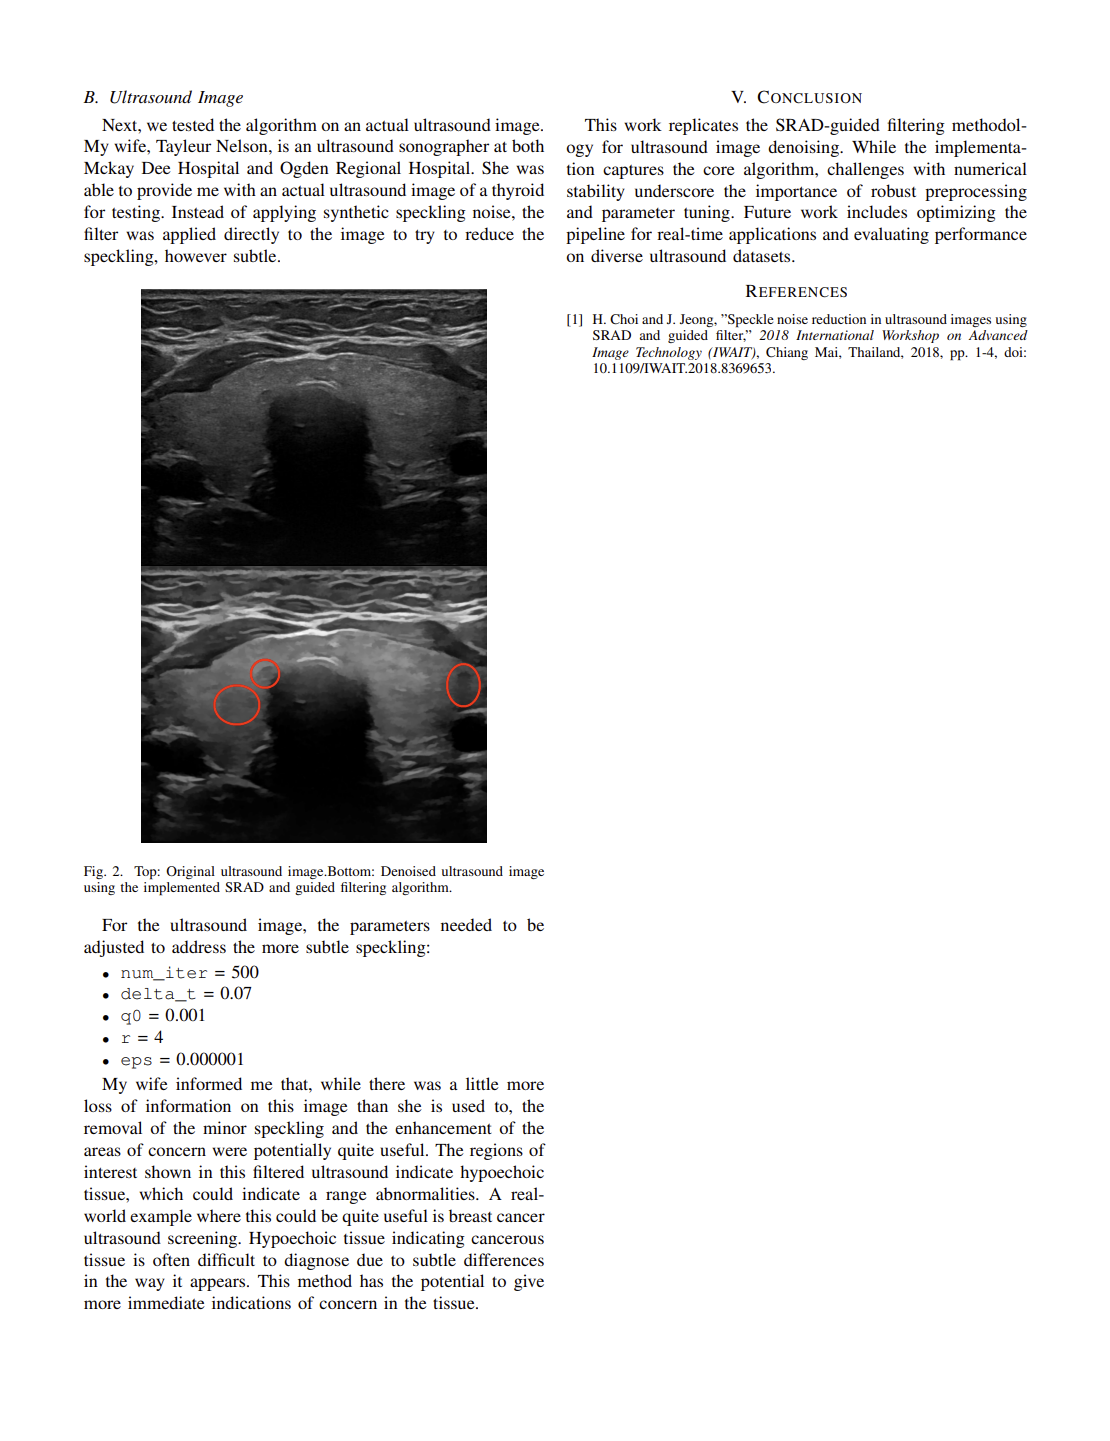

Replication study on ultrasound speckle reduction methods and output comparison.